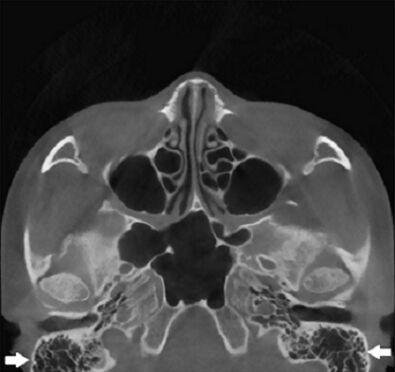

66.所附電腦斷層影像中,白色箭頭所指為下列何者? (A)篩竇(ethmoid sinus) (B)蝶竇(sphenoid sinus) (C)上顎竇(maxillary sinus) (D)乳突氣房(mastoid air cells/mastoid process)